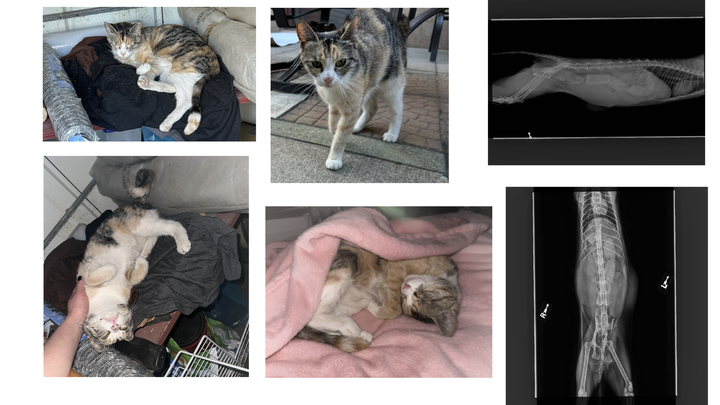

During the first vet visit I had asked if she might be pregnant, and noticed she walked strangely to which the first vet told me she was perfectly healthy and was not likely pregnant. Upon seeing another doctor and emergency vet, it's been uncovered that she was hit by a car, pregnant with three kittens, and severely constipated (this has now turned into obstipation as I type)

The car hitting her has caused her pelvis bones to break in a way that's causing her to be constipated/obstipation and is posing a danger to not only herself but her three kittens, as she is unable to defecate or give birth to these kittens.

I received the call this morning around 9:30AM on August 1st 2025 after two long visits to the emergency vet and was notified that they would need to perform surgery to relieve her constipation / manually extract obstipation, save or remove her uterus and babies, and potentially amputate her leg. The quote I was given was anywhere between $8k - 13k, increased up to over 20k based on any complications (amputation, c section, medication) . I'm attempting to take out a loan that I'm unsure will get approved for and I'm currently using Scratchpay to support her, but I have run out of options. Scratchpay has only granted me $8k, all donations will go towards the rest of her bill as needed to save her life.